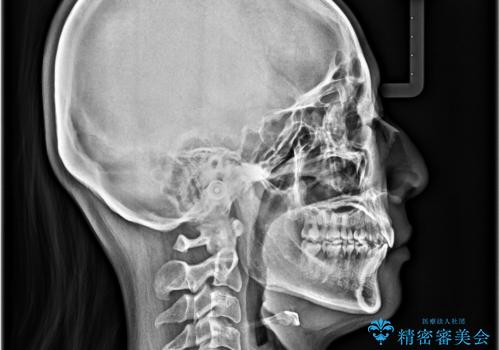

- 前歯の突出感とデコボコを気にして来院された患者様です。

奥歯の噛み合わせをみると、上顎歯列が全体的に前突している状態であり、この咬み合わせのまま歯列を整えると出っ歯になってしまう可能性がありました。

アンカースクリューと補助装置を使用して上顎大臼歯を遠心移動させることで咬み合わせを改善し、ワイヤー装置によりデコボコを解消しながら口元の突出感も改善していくこととしました。

出っ歯になることなく、上下前歯が綺麗に接触する状態で仕上げることができました。